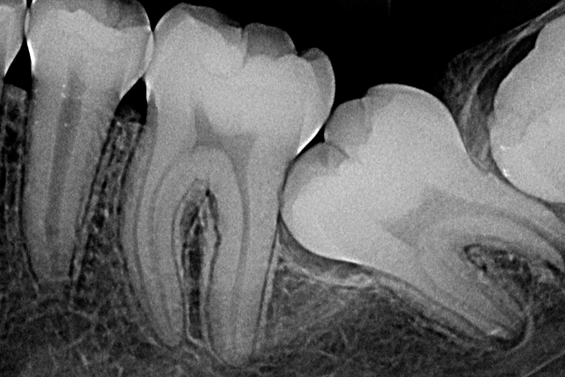

Radiografias Periapicais Digitais

Tem como objetivo visualizar os ápices das raízes dos dentes e das estruturas que os rodeiam. É utilizada para pesquisa e lesões periapicais e periodontais, fraturas, anomalias, reabsorções e outras lesões que atingem os dentes.

O Levantamento Periapical é o exame mais completo dentro do grupo das radiografias periapicais, sendo

composto de 14 radiografias.